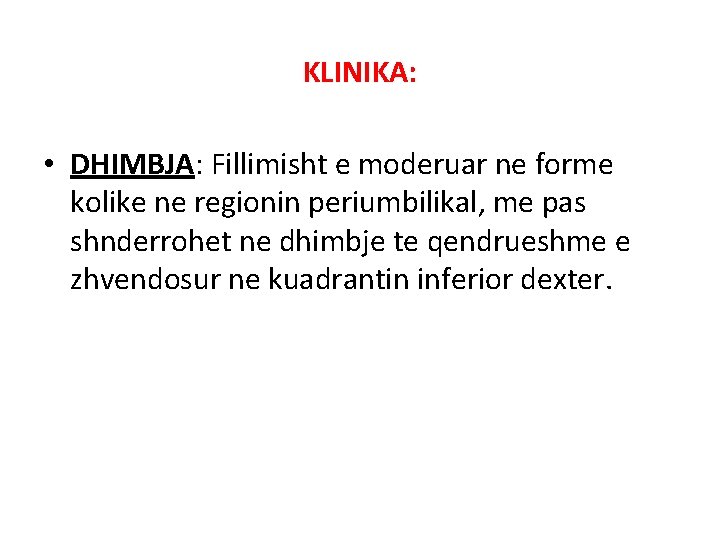

KLINIKA: • DHIMBJA: Fillimisht e moderuar ne forme kolike ne regionin periumbilikal, me pas shnderrohet ne dhimbje te qendrueshme e zhvendosur ne kuadrantin inferior dexter.